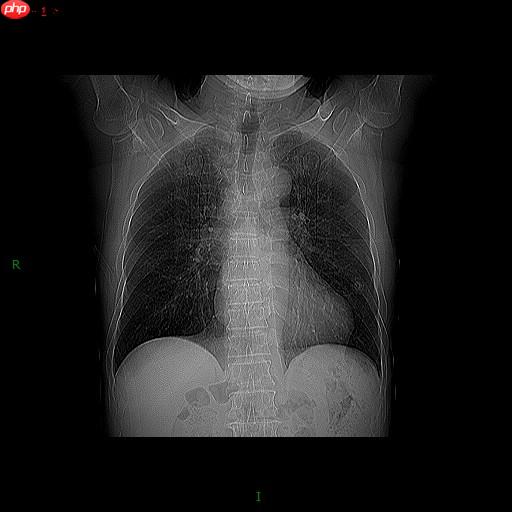

PS:数据来源于胸部x光肺部分割数据,并进行了一定的处理后再展示使用。【部分展示】

我们来看原图

再看mask(0,1取值)

一片漆黑,啥也看不到,都不知道它分割的是哪部分。为了把mask“显形”就可以通过下面的程序进行处理,处理后就会变成这样的结果。经处理后我们就可以清晰看到原图的mask的到底是哪一部分